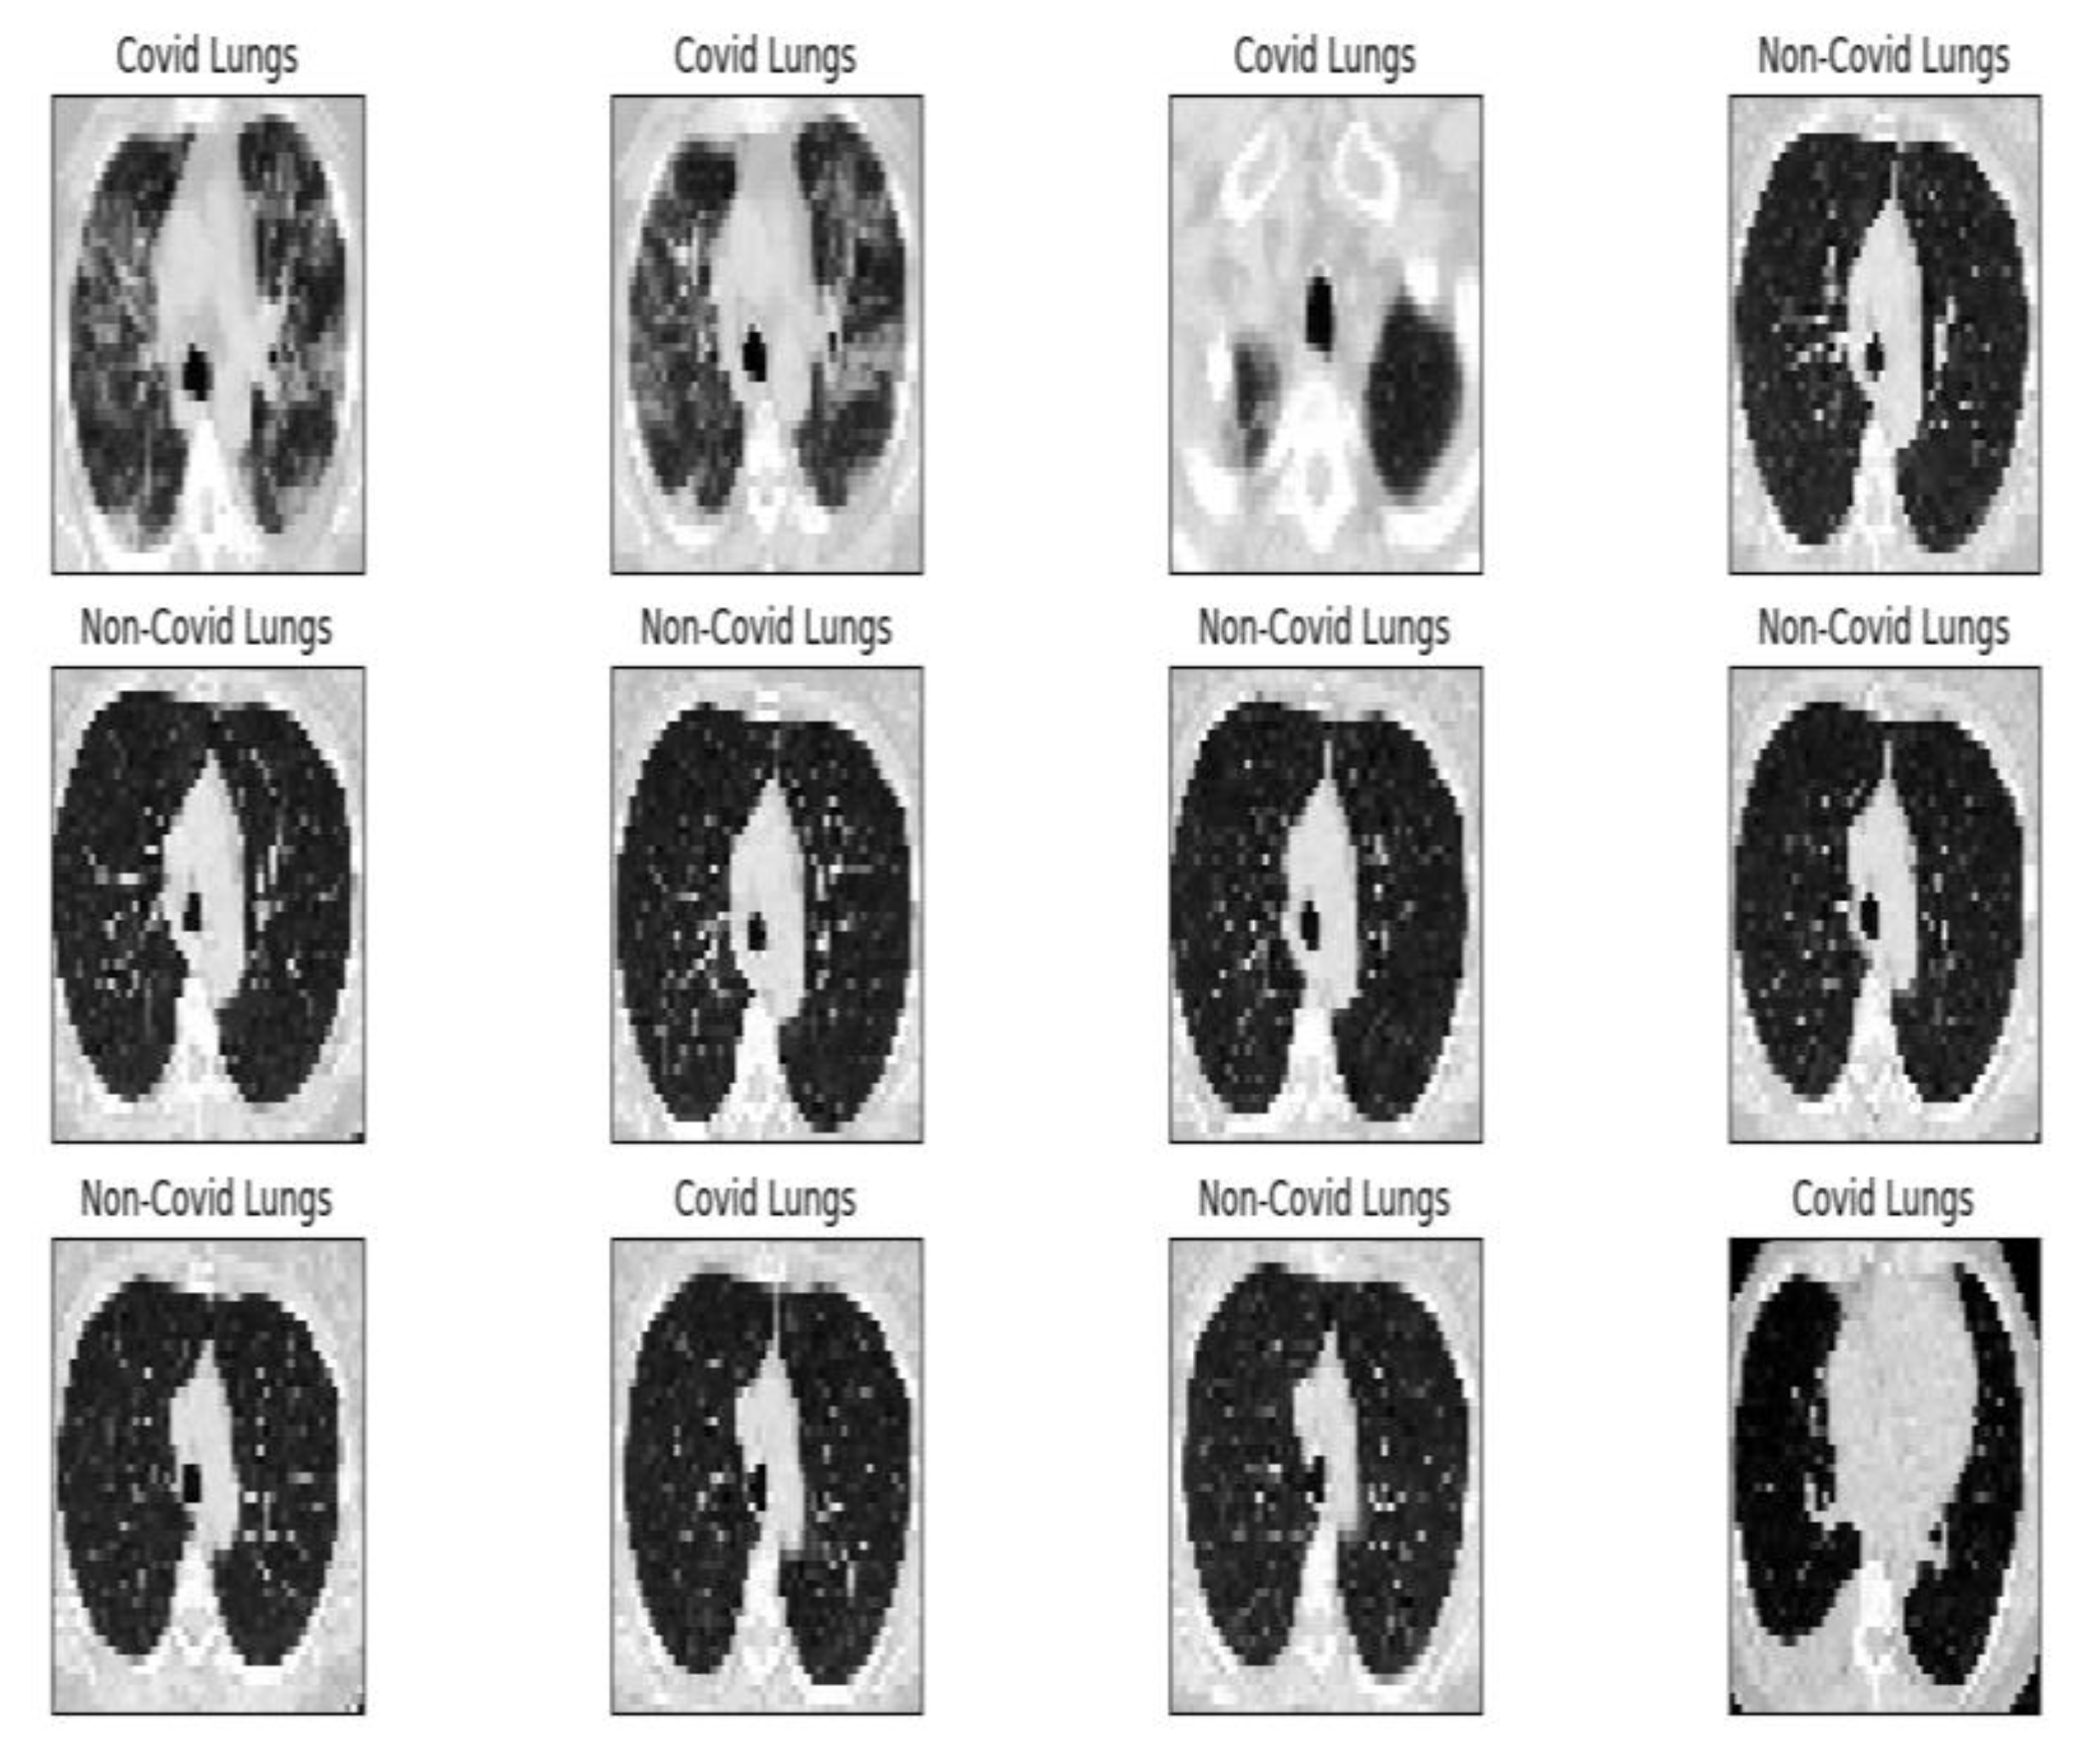

Project development started by establishing the data set according to the objective. For this, we used a public data set provided by the www.kaggle.com platform. The set comprises 2481 images (1251 contain lungs with COVID-19 infection and 1230 contain lungs without COVID-19 infection). At the beginning of the program, each image receives the appropriate label, “covid” or “normal”, which is resized to 50 × 50 pixels (see Figure 2) and undergoes conversion to grayscale (grayscale format). After these transformations, the image–label pair is passed as an entry in an array. Further, a block list containing the values of the main parameters used in the inference process is presented in Figure 3.

Figure 8 shows the complete module of some lung CT images affected by COVID-19 and images of lungs that did not suffer from COVID-19, unaffected by the virus, practically healthy lungs.

We mention that the set of images from Figure 8 and the license to use them can be found online at the address indicated in the bibliographic reference [21].

Figure 8. Image validation of the completed module.